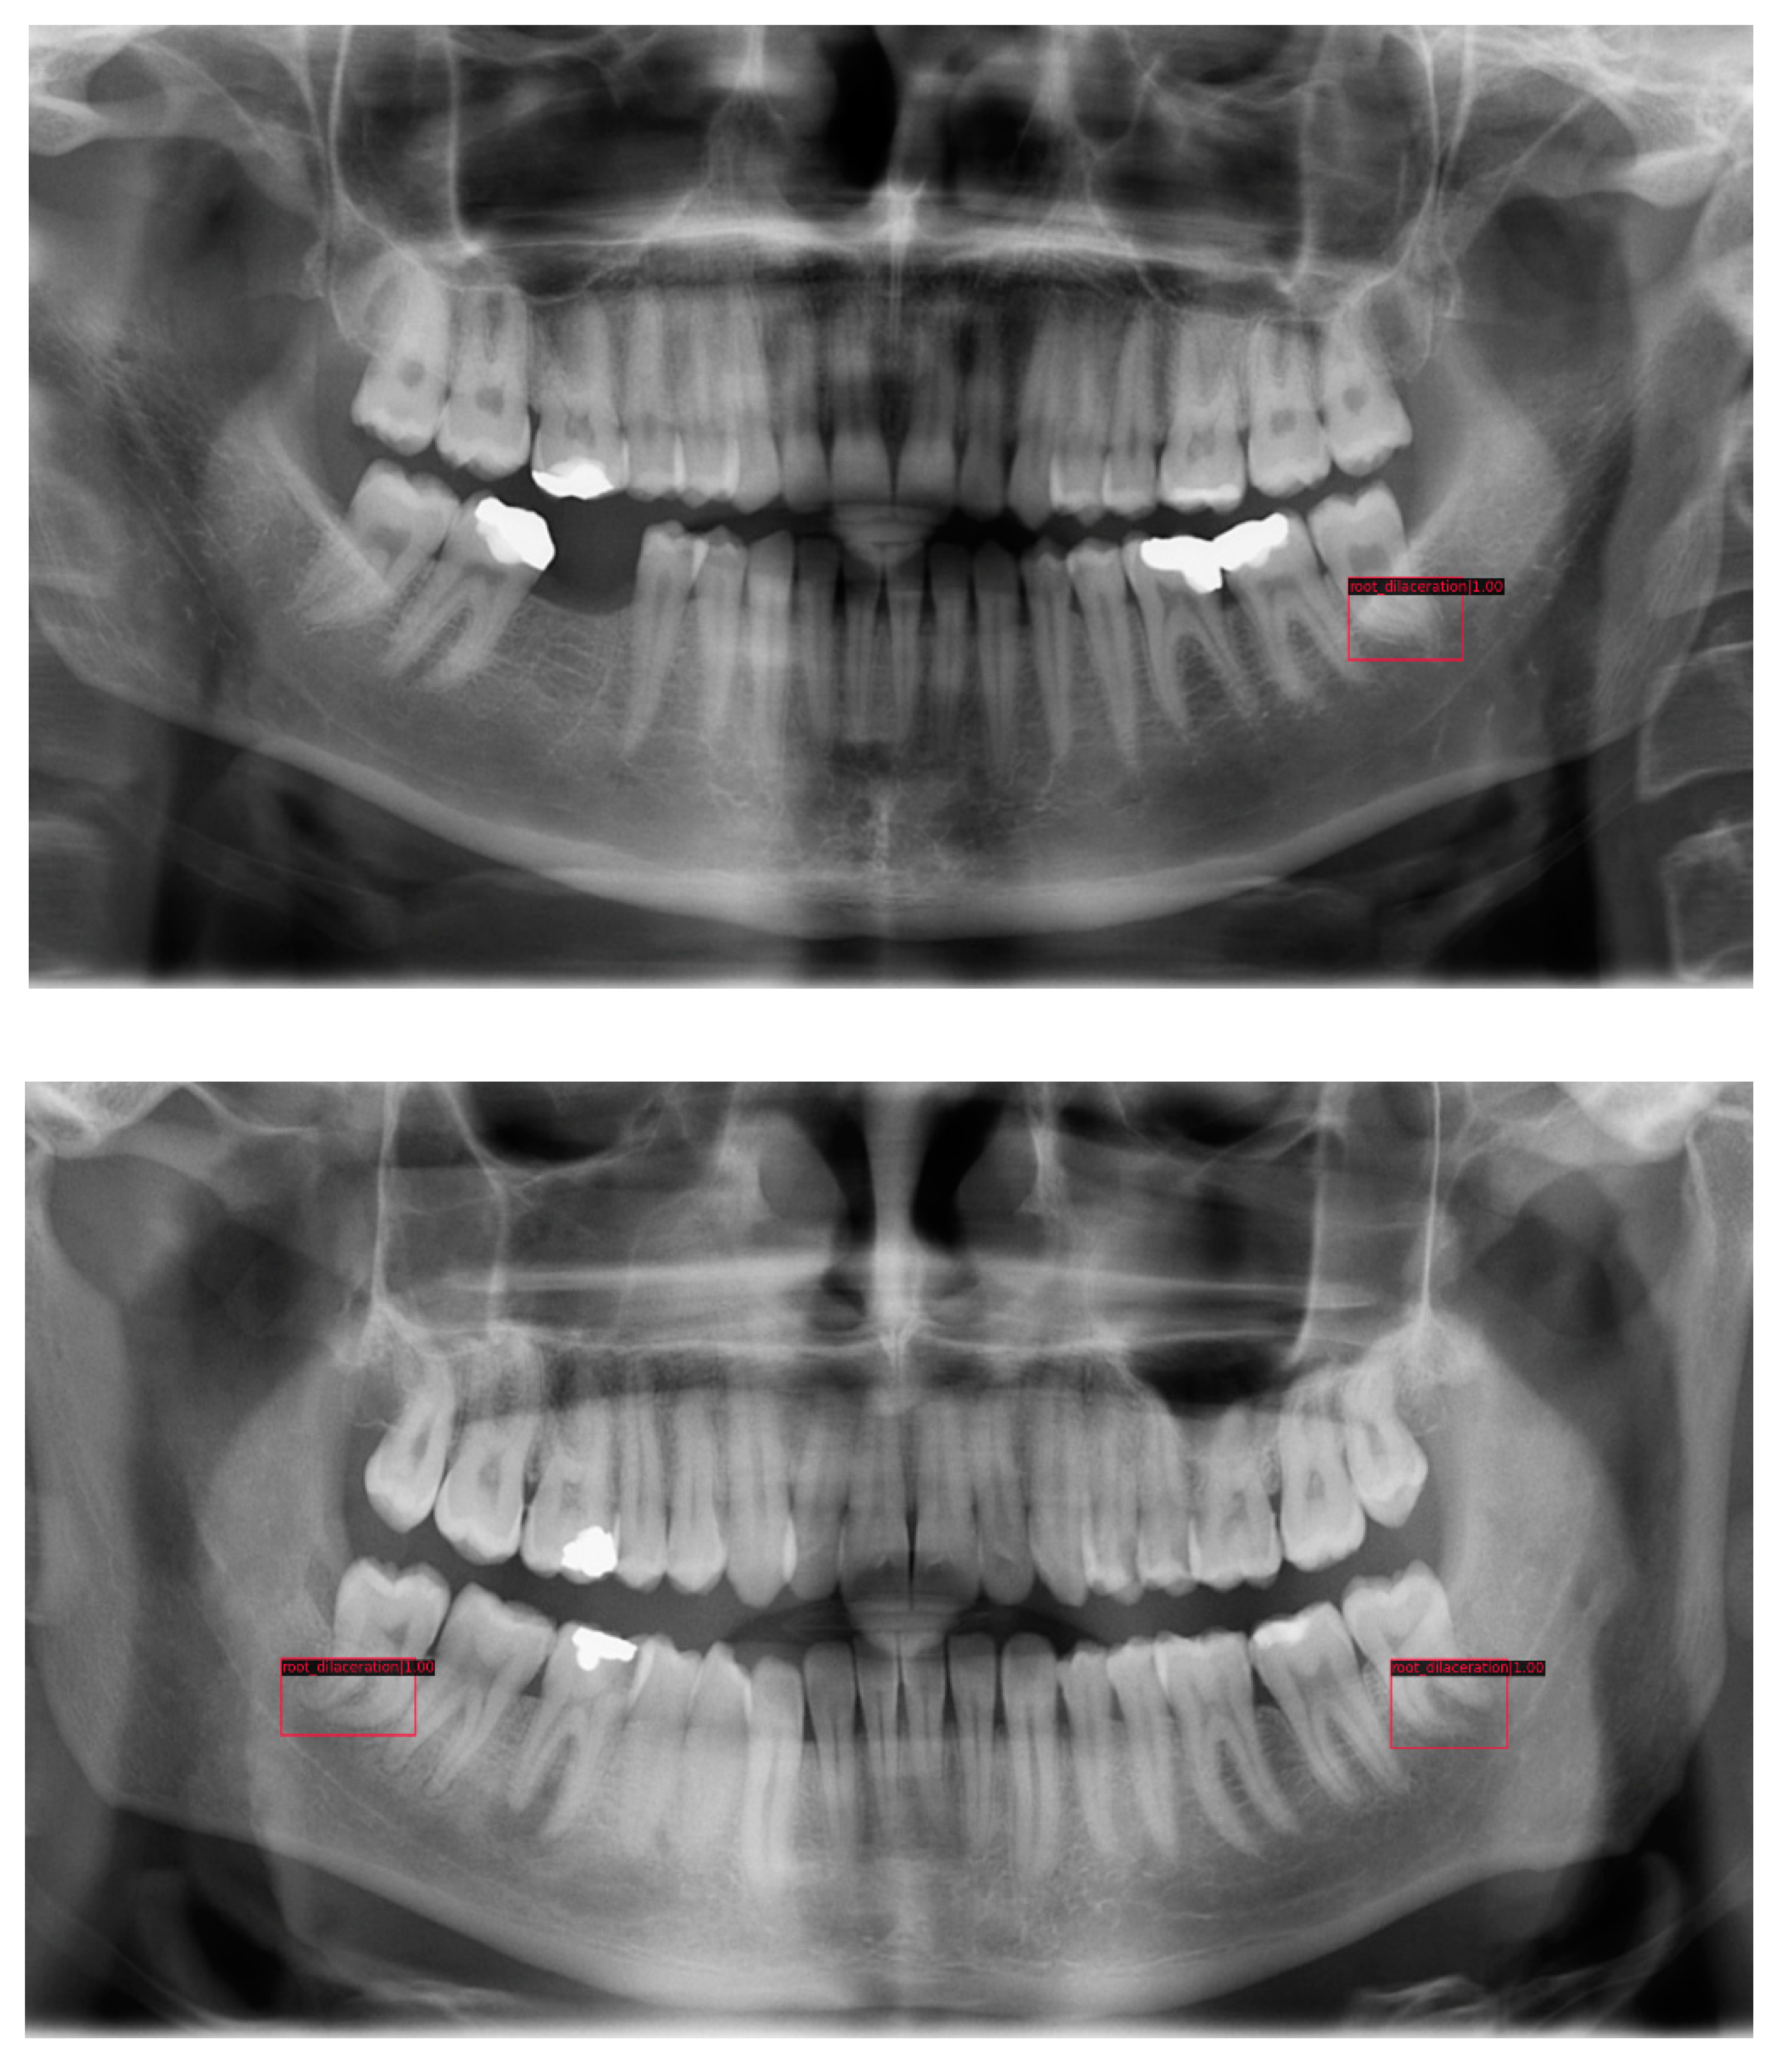

The detection performance of the models was analyzed by mAP that varied between 0.68 and 0.92. Except SSD, all other models successfully detected root dilacerations with a success rate higher than 0.83. The best two models were FreeAnchor Resnet50 and Cascade RCNN Resnet101 with 0.92 and 0.9. Accuracy varied between 0.48 and 0.72, and the best accuracy was provided by the Cascade RCNN Resnet101 and RetinaNet Resnet50 models with 0.72. Precision varied between 0.66 and 0.91. Faster RCNN Resnet101, Libra RCNN Resnext101 and FreeAnchor Resnet50 showed the highest precision with 0.91. Recall varied between 0.59 and 0.87. Faster RCNN with weight standardization (WS) and batch-channel normalization (BCN) and RegNetx provided the highest recall with 0.87 and 0.86. F1 score varied between 0.65 and 0.83. Cascade RCNN Resnet101 and RetinaNet Resnet50 were superior to the others with 0.83. The training time for each model is also given in Table 1. Libra RCNN Resnext101 had the longest training time whereas RetinaNet Resnet50 was trained at the earliest. Figure 3 illustrates model predictions for root dilacerations with predicted bounding boxes and labels.

Figure 3.

Example of test process of root dilaceration detection. Model outputs/predictions are shown in rectangular boxes with corresponding labels.